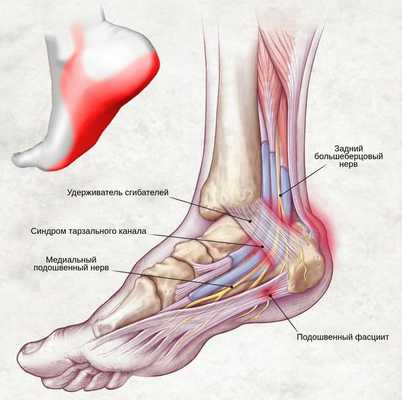

Синдром тарзального (предплюсневого) канала — это периферическая мононевропатия нижней конечности, которая возникает в результате сдавления большеберцового нерва, проявляющаяся болью в области голеностопного сустава по внутренней стороне стопы.

На уровне голеностопного сустава большеберцовый нерв проходит через жёсткий остеофиброзный туннель — тарзальный канал. [1] Это пространство спереди ограничено большеберцовой костью, а снаружи — задним отростком таранной кости и пяточной костью, а также удерживателем сгибателей (сухожилий).

Анатомически в канале сосуществуют несколько сухожилий мышц: задняя большеберцовая, сгибатель большого пальца и длинный сгибатель пальцев. [8] [9] Причём короткий и длинный сгибатели большого пальца стопы являются основными мышцами, которые получают иннервацию после выхода нерва из канала предплюсны.

Ишемическая компрессия содержимого тарзального канала приводит к изменению кровообращения в стопе и слабости короткого сгибателя большого пальца стопы. Хроническое сдавление в результате нарушения той же иннервации способствует деформации по типу молоткообразных (кошачьих) пальцев. Также отмечается, что патология сопутствует почти каждому случаю вальгусной деформации стопы.